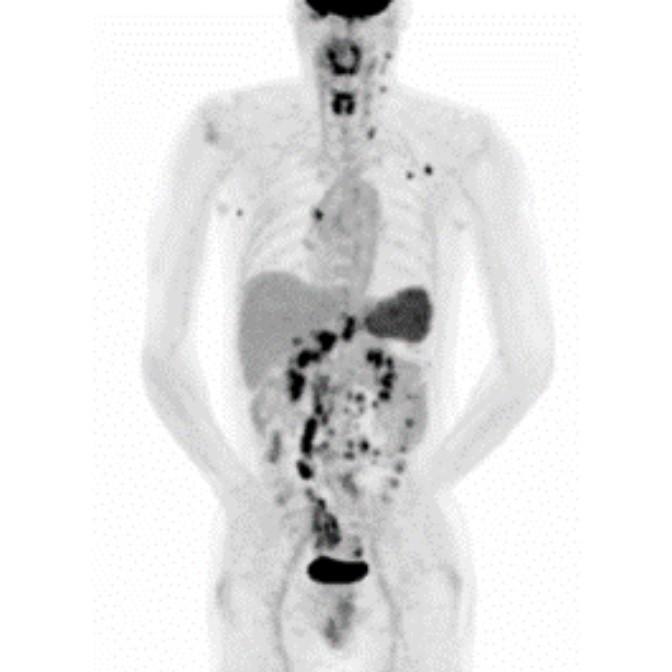

Partial nml and melanoma PET scan